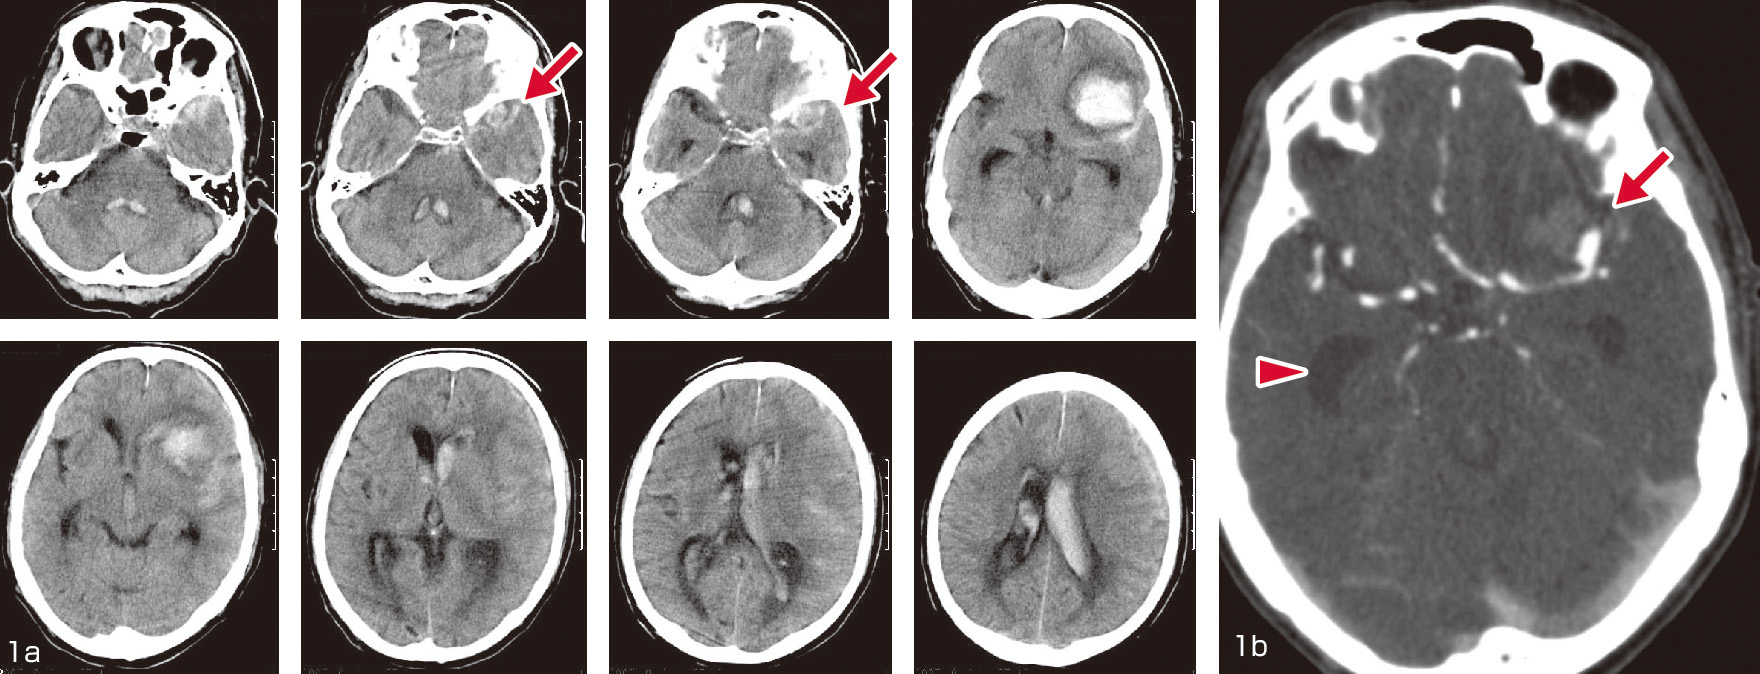

中外医学社 | 書籍詳細。臨床心臓CT学-基礎と実践マネージメント | 小山 靖史, 鈴木 諭。アプリケーション(心臓領域) | REVORAS。【N☆】令和6年(新米)コシヒカリ1等米10キロ。CT検査 | 戸畑共立病院。オプション検査 | 人間ドック健診センター | 大田区蒲田 牧田。。桜橋渡辺未来医療病院 MDCT検査予約。医学出版_循環器ナーシング16年6月号。CT検査 | 戸畑共立病院。心臓特化型画像診断センター「心臓画像クリニック(CVIC)飯田橋。朝倉書店『内科学』(第12版)デジタル付録。メジカルビュー社|診療放射線技師|心臓CT活用マニュアル。心臓Ⅰ:Step and shoot technique 岩城 卓(横浜栄共済病院。「臨床心臓CT学 基礎と実践マネージメント」小山 靖史定価: 22000円 (20000円+税)ぼぼ未使用でパラパラと見ただけで、状態はよいと思われます。書き込みも見返しましたがありませんでした(万が一あったら申し訳ございません)。表面に多少のスレやキズはあります。また天面に名前の印鑑がありマジックで消しています。あくまで写真のものをお渡しということでよろしくお願い致します。ご質問や価格交渉ありましたらメッセージくださいm(._.)m循環器内科、内科、カテ、カテーテル、CAG、PCI、FFRインターベンション、読影、放射線冠動脈、動脈硬化冠動脈疾患、虚血性心疾患、狭心症、心筋梗塞高血圧、糖尿病、脂質異常症、肥満